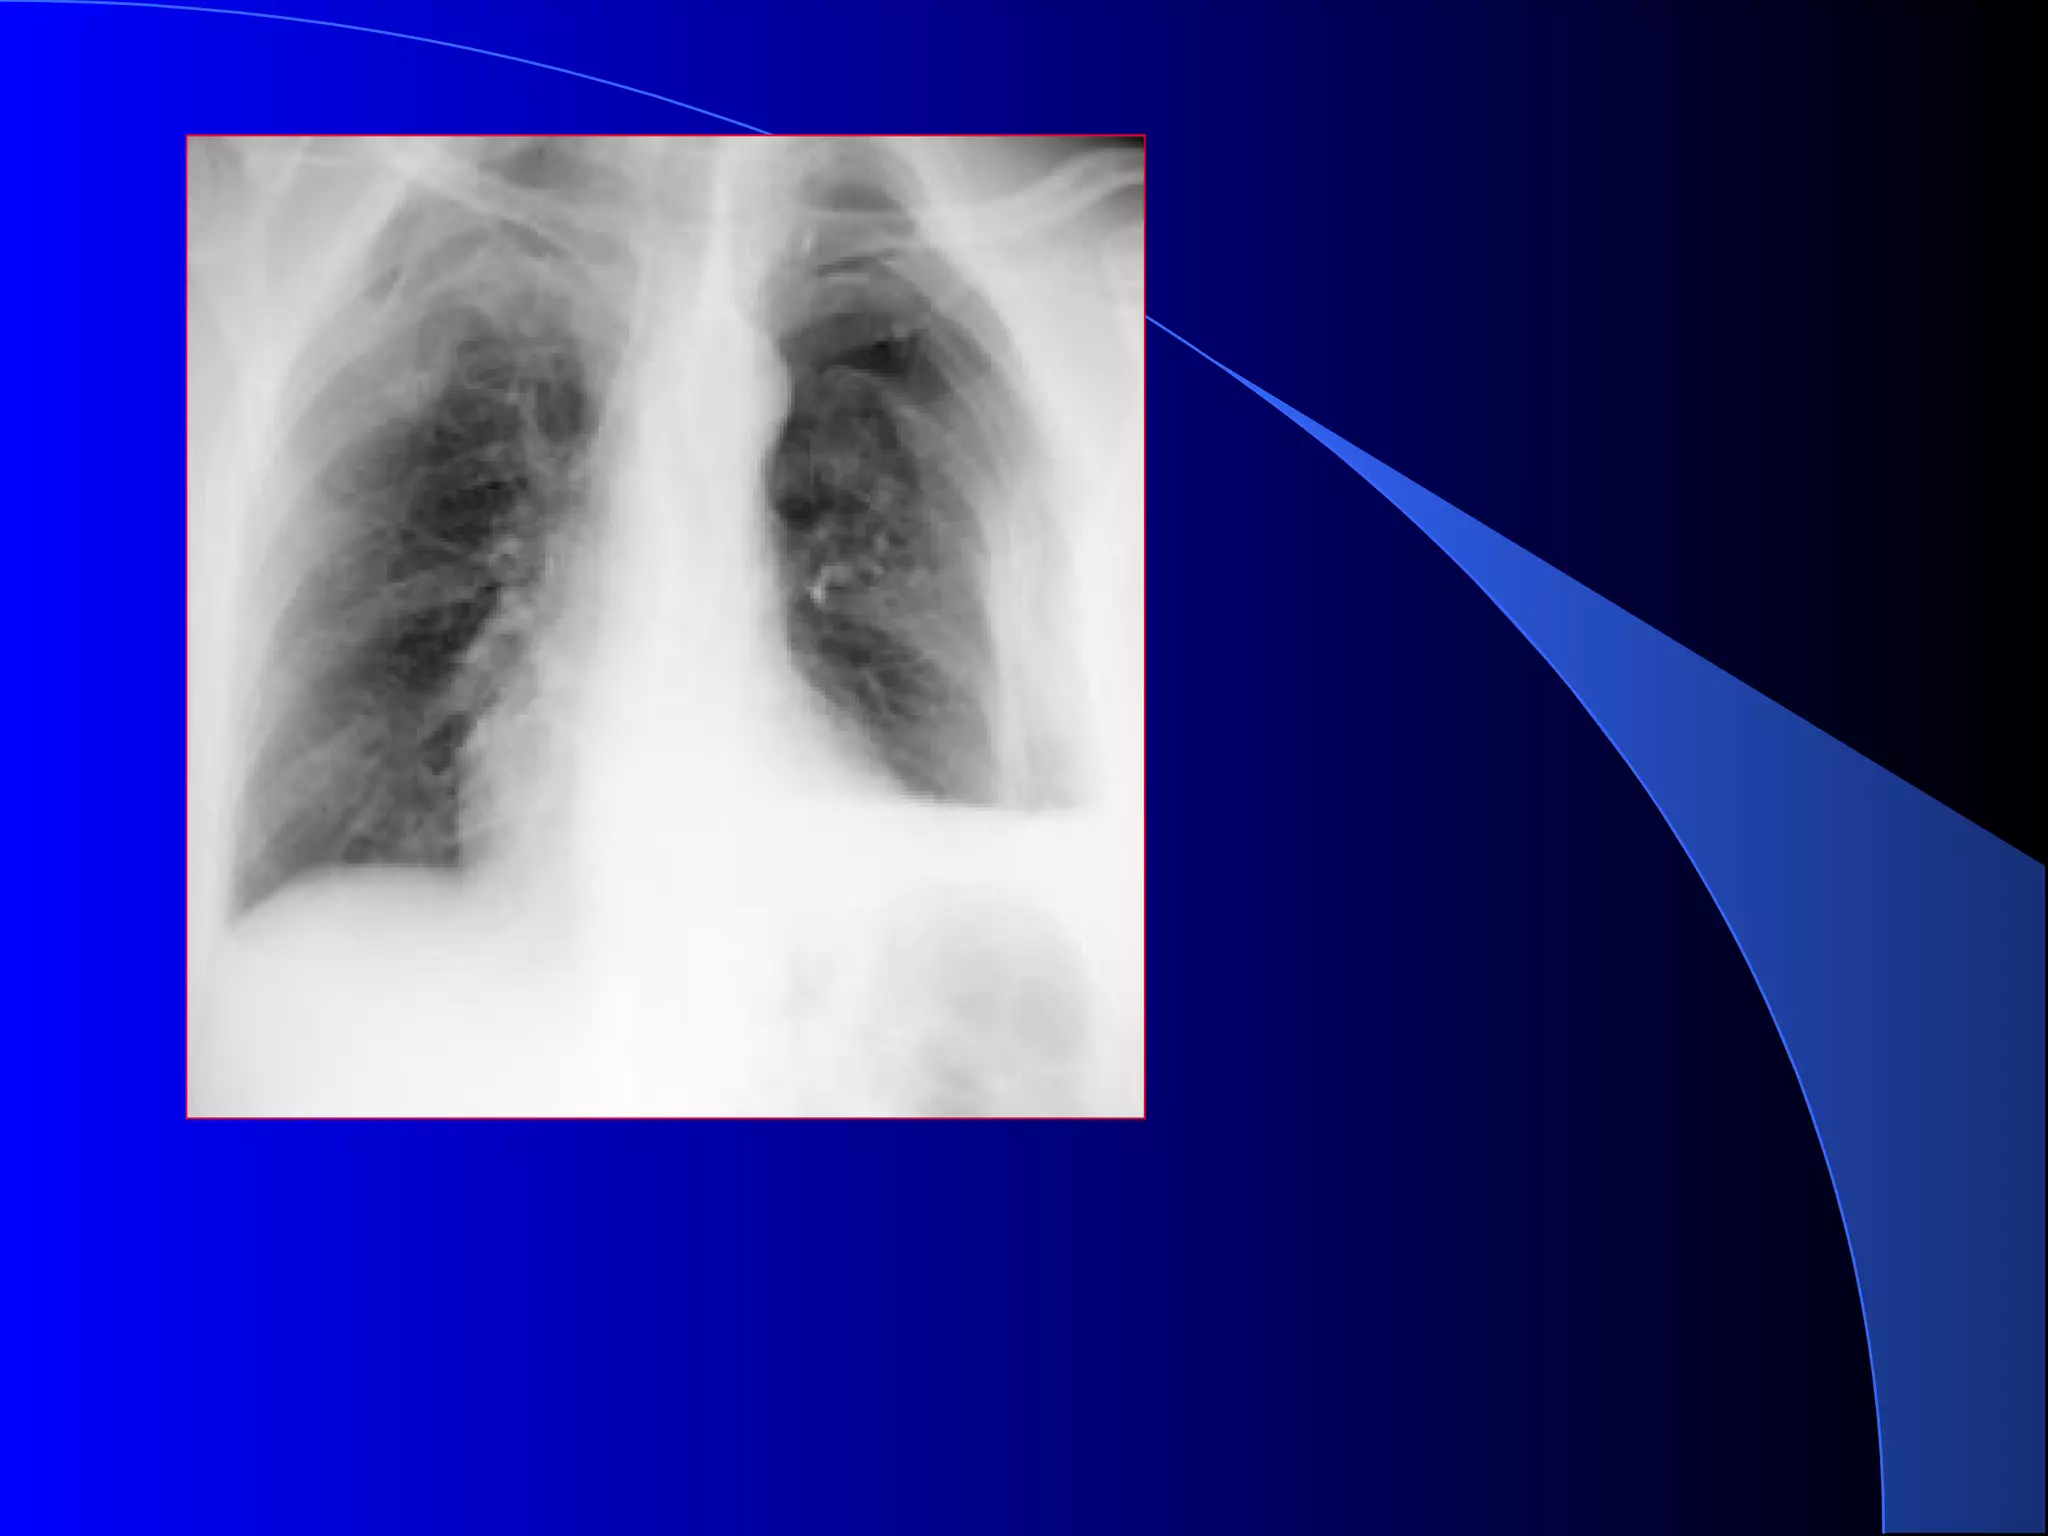

PNEUMOTORAX SUFOCANTPNEUMOTORAX SUFOCANT

 Pneumotorax total sting cu

deplasarea controlaterala a

mediastinului

fracturi costale

plaman colabat la hil

PNEUMOTORAX SUFOCANTPNEUMOTORAX SUFOCANT Pneumotorax total sting cu deplasarea controlaterala a mediastinului fracturi costale plaman colabat la hil